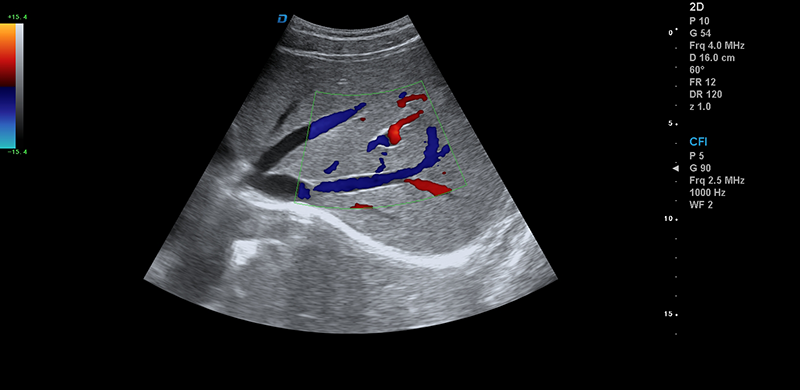

肝臟靜脈血流